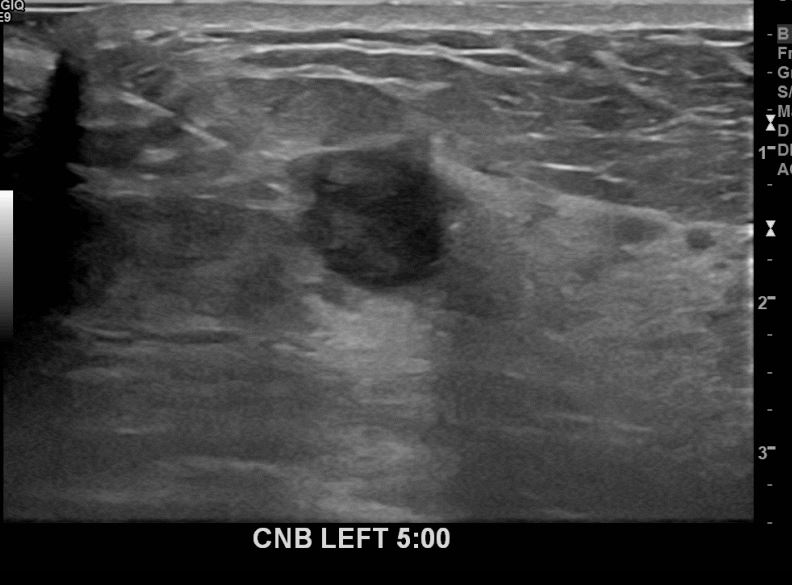

상기환자 경과관찰중인 50대여성으로 좌측에 의심스러운혹 조직검사시행해 유방암 진단되었습니다.